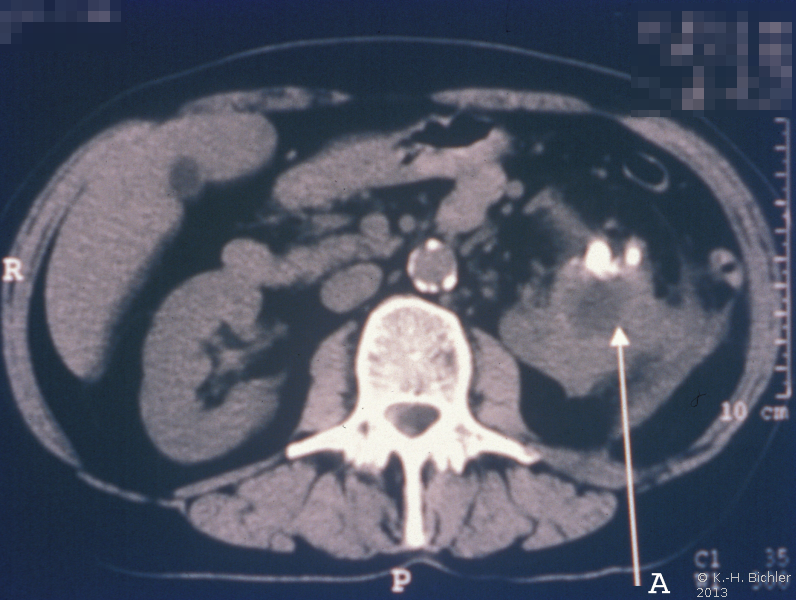

Sie tritt zumeist bei Patienten mit Diabetes Mellitus bzw. bei Harnwegsobstruktionen auf (Komplizierte Pyelonephritis). Dabei können eine oder alle Papillen befallen sein. Histologisch findet sich eine koagolative Infarktnekrose, d.h. die Umrisse von befallenen Tubuli sind erhalten. Leukozytäre Reaktionen finden sich an den Rändern der Nekrosebezirke Literatur:Robbins: "Pathologic Basis of Disease", Saunders Philadelphia, 1999.